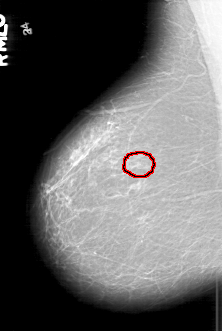

D_4196_1.RIGHT_MLO

RIGHT_MLO LINES 6271 PIXELS_PER_LINE 4216 BITS_PER_PIXEL 12 RESOLUTION 43.5 OVERLAY

FILE: D_4196_1.RIGHT_MLO.OVERLAY

TOTAL_ABNORMALITIES 1

ABNORMALITY 1

LESION_TYPE CALCIFICATION TYPE PLEOMORPHIC DISTRIBUTION CLUSTERED

ASSESSMENT 0

SUBTLETY 5

PATHOLOGY BENIGN

TOTAL_OUTLINES 1

BOUNDARY